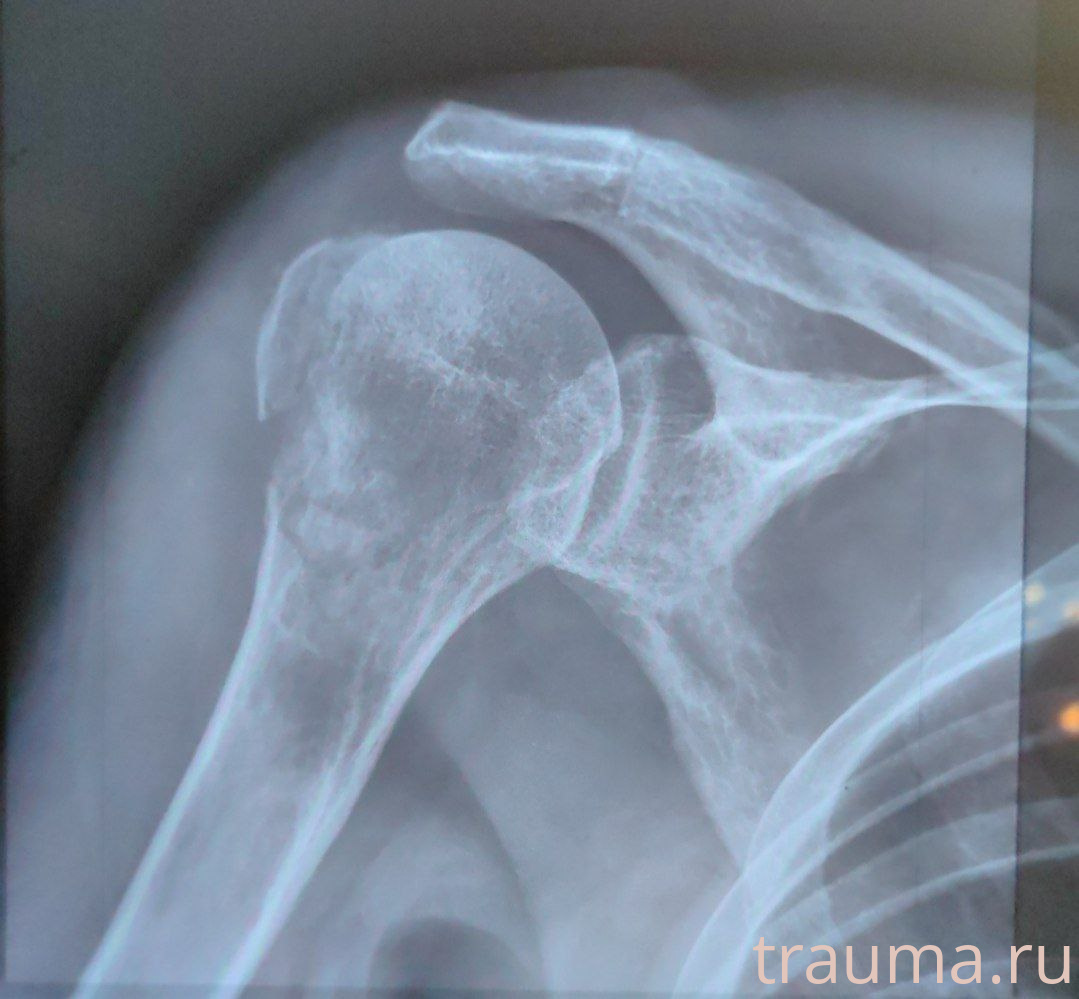

Рентгенограммы

Рентген на дому: по вашему адресу приезжает врач-рентгенолог, травматолог-ортопед с мобильным рентгеновским аппаратом, проводит диагностику травмы или заболевания, делает необходимые рентгенограммы, дает рекомендации по дальнейшему лечению. Получить качественные снимки в домашних условиях возможно благодаря уникальной методике, разработанной МосРентген Центром для института  Склифосовского